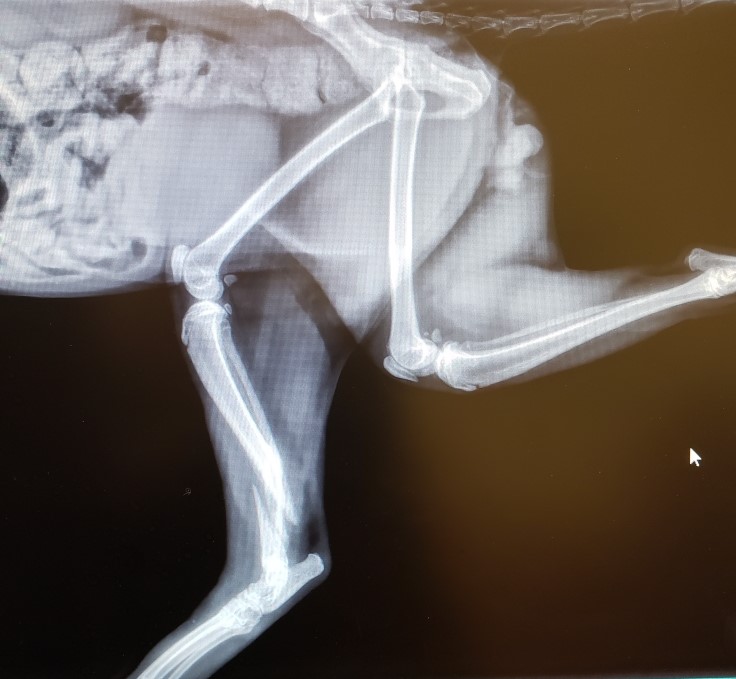

The story of a stray cat, a broken foot, and lots of love